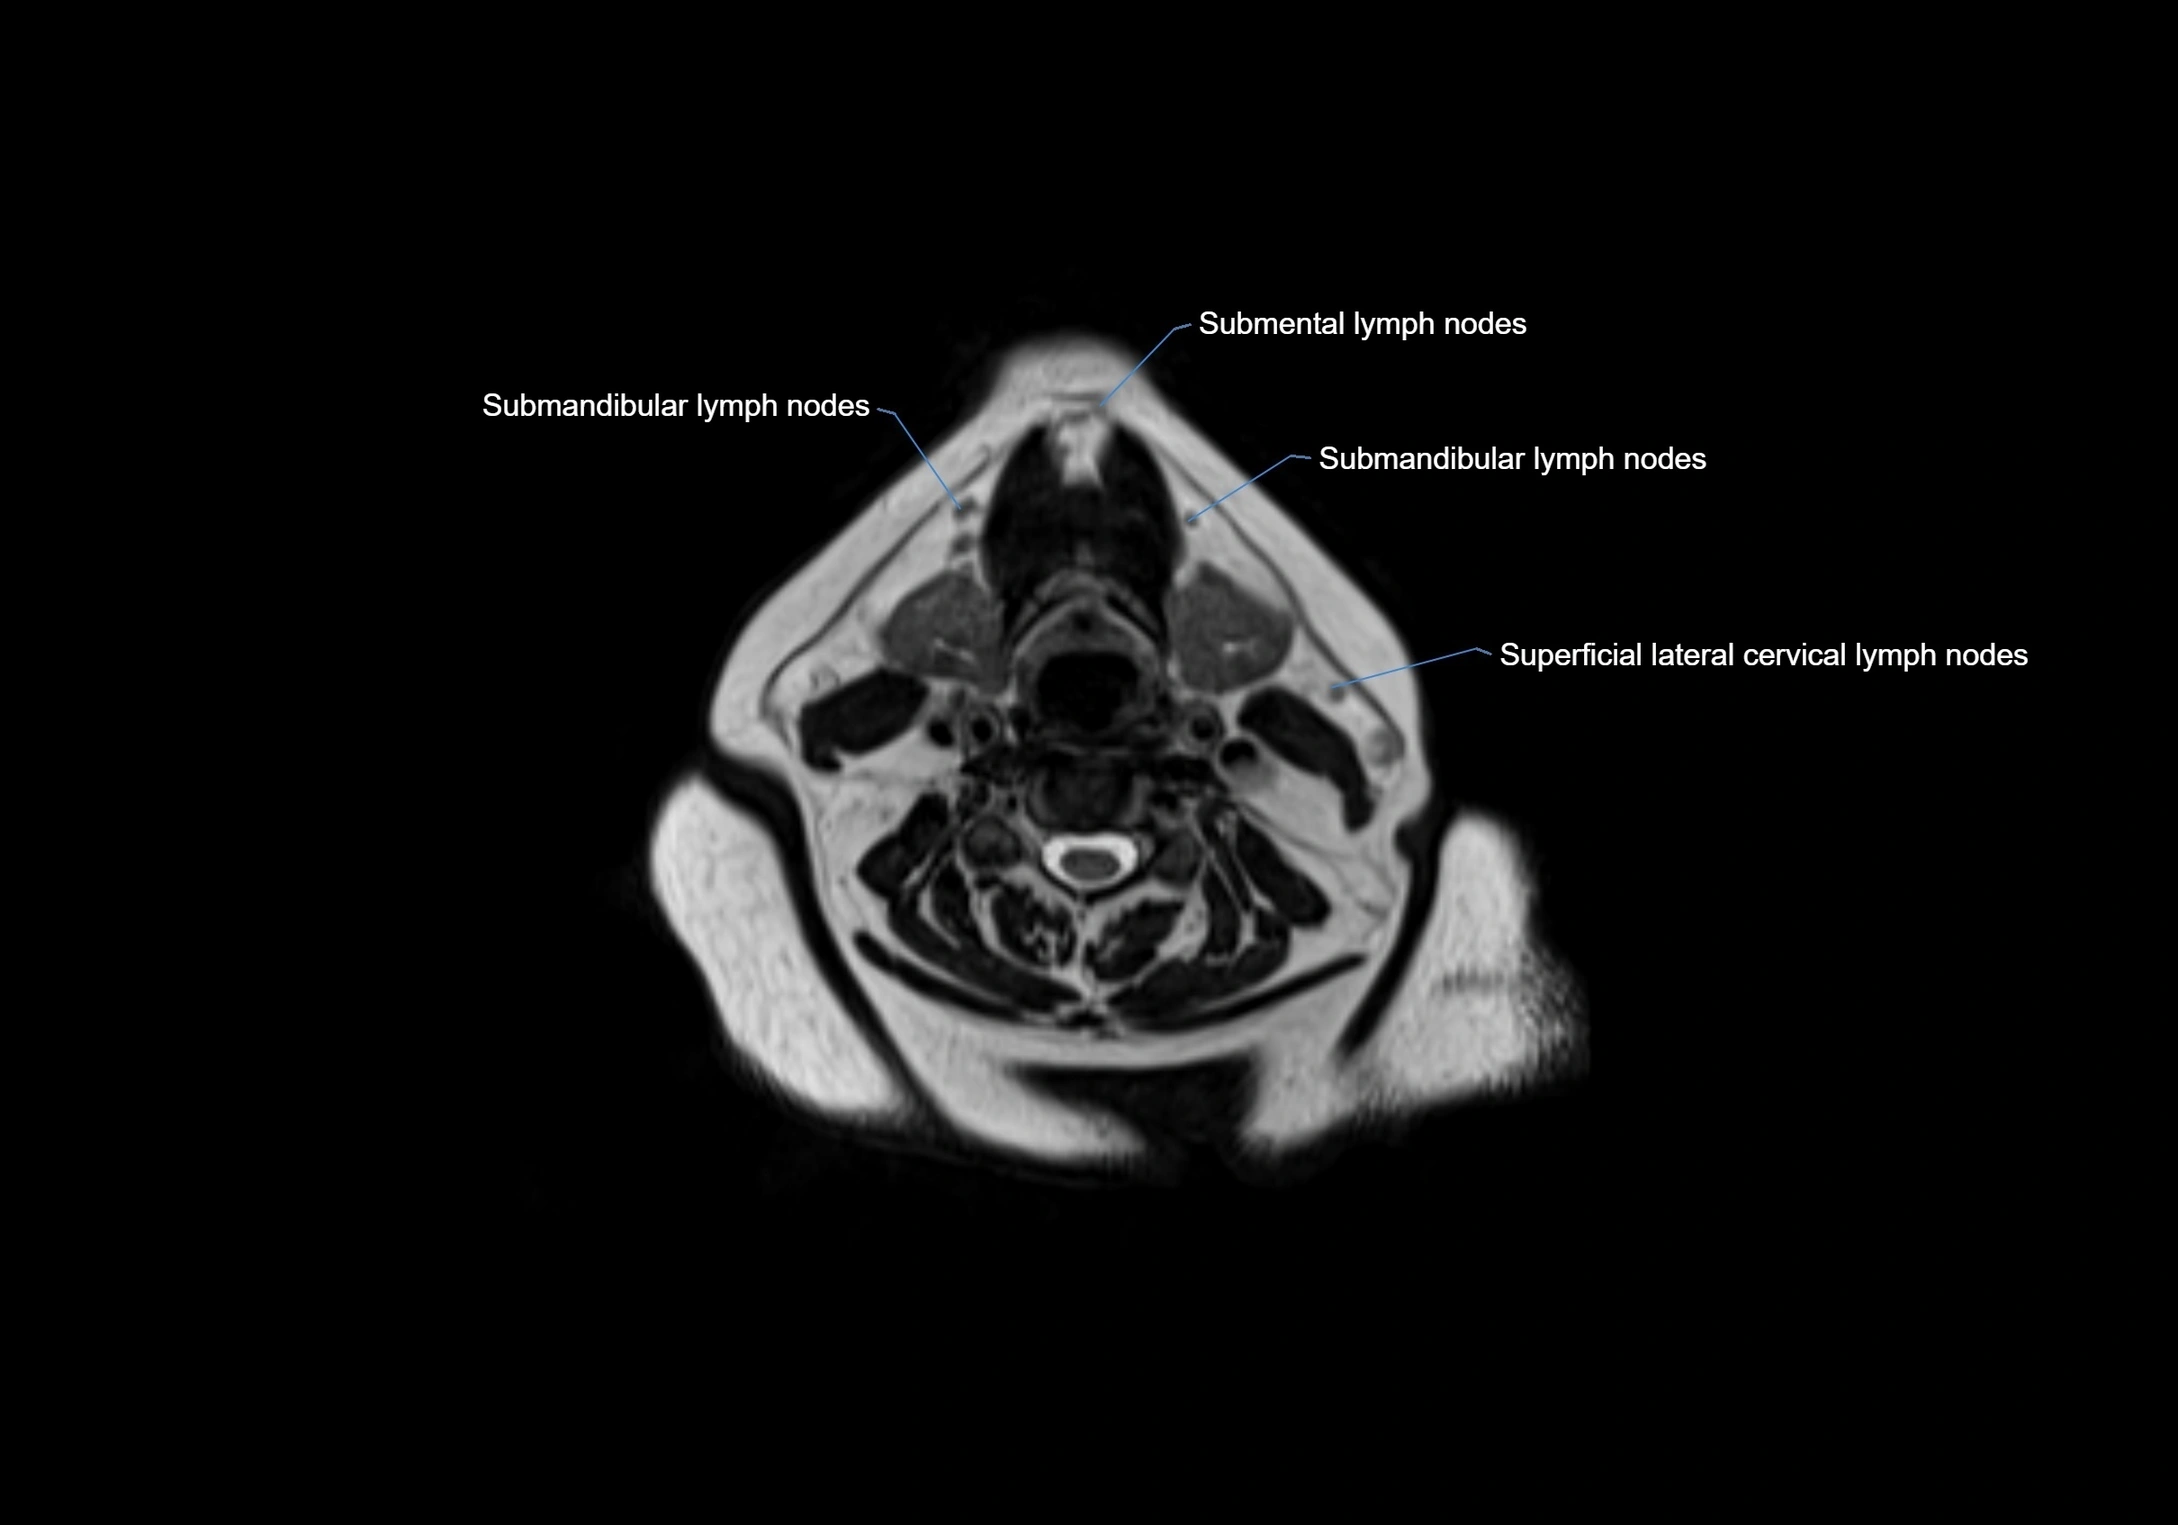

MRI images

image